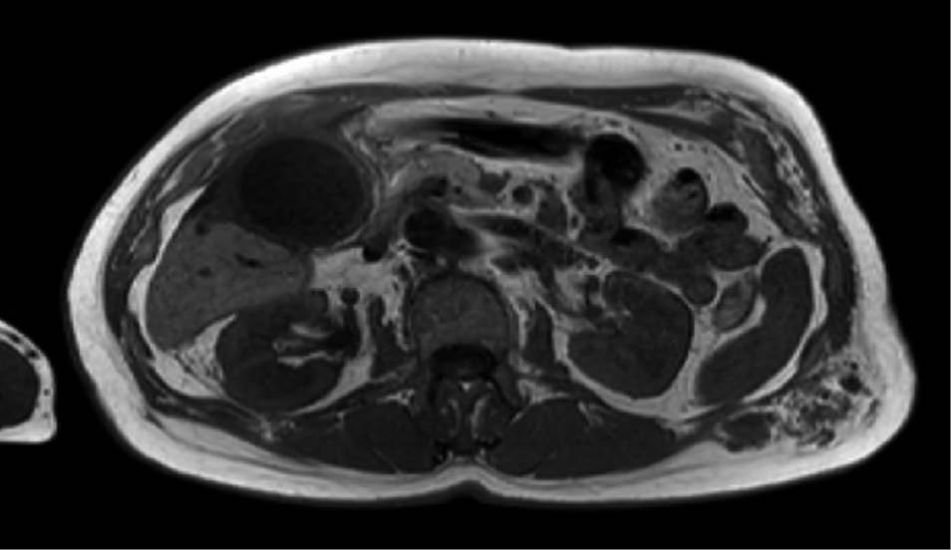

Laparoskopische Cholezystektomie für symptomatische Cholezystolithiasis (CCL) bei „Kasabach-Merritt-Syndrom“ (KMS)